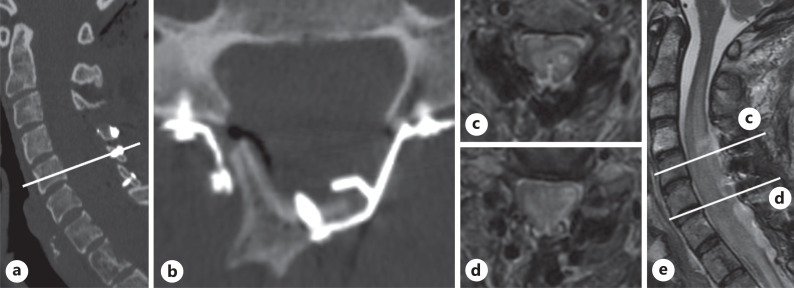

Case presentation: A 53-year-old female with a history of mediastinal Hodgkin lymphoma treated with chemotherapy and radiotherapy who subsequently developed thyroid cancer and breast cancer throughout her life was admitted due to slowly progressing spastic tetraparesis. Cervical MRI revealed an intramedullary lesion at the C4-T1 level, enlarging the spinal cord, with a heterogenous contrast enhancement and a lesion within T1 vertebral body showing contrast enhancement. Whole-body 18F-FDG-PET/CT revealed increased radionuclide uptake within the cervical spinal cord at the C2-C7 level and a focus of increased metabolic activity within the T1 vertebral body. The patient underwent a C4-T2 laminectomy with tumor debulking, and a biopsy of the T1 vertebral body was taken. Closure was performed with thecal sac expansion using a fascia lata graft and open-door laminoplasty. The histomolecular results confirmed the diagnosis of glioblastoma, IDH-wildtype (CNS WHO G4), in the cervical spinal cord lesion and breast cancer metastasis in the T1 vertebral body. Postoperatively, the patient experienced progression of lower extremities and left arm paresis. No adjuvant therapy was administered due to neurological deficit progression. The patient died 6 months after surgery.